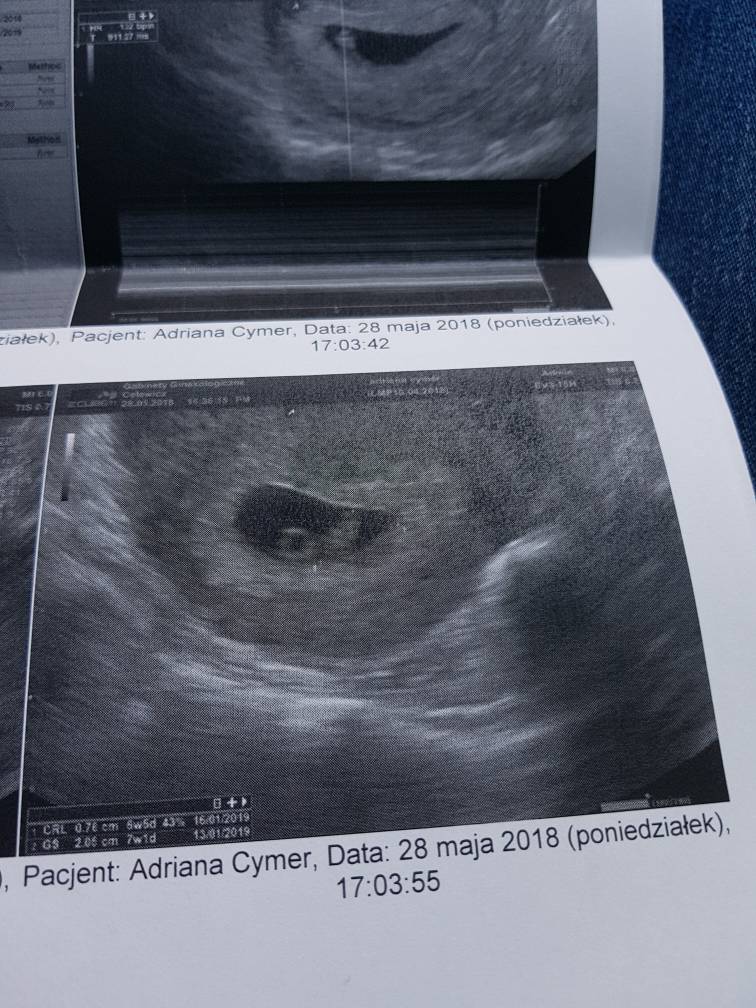

Już po wizycie [emoji4] serduszko pika [emoji173] [emoji173] [emoji173] Tętno 134[emoji173]

Lekarz mówi, że wszystko jest idealnie [emoji4]

Termin z USG na 15.01 :-)

A oto mój Groszek